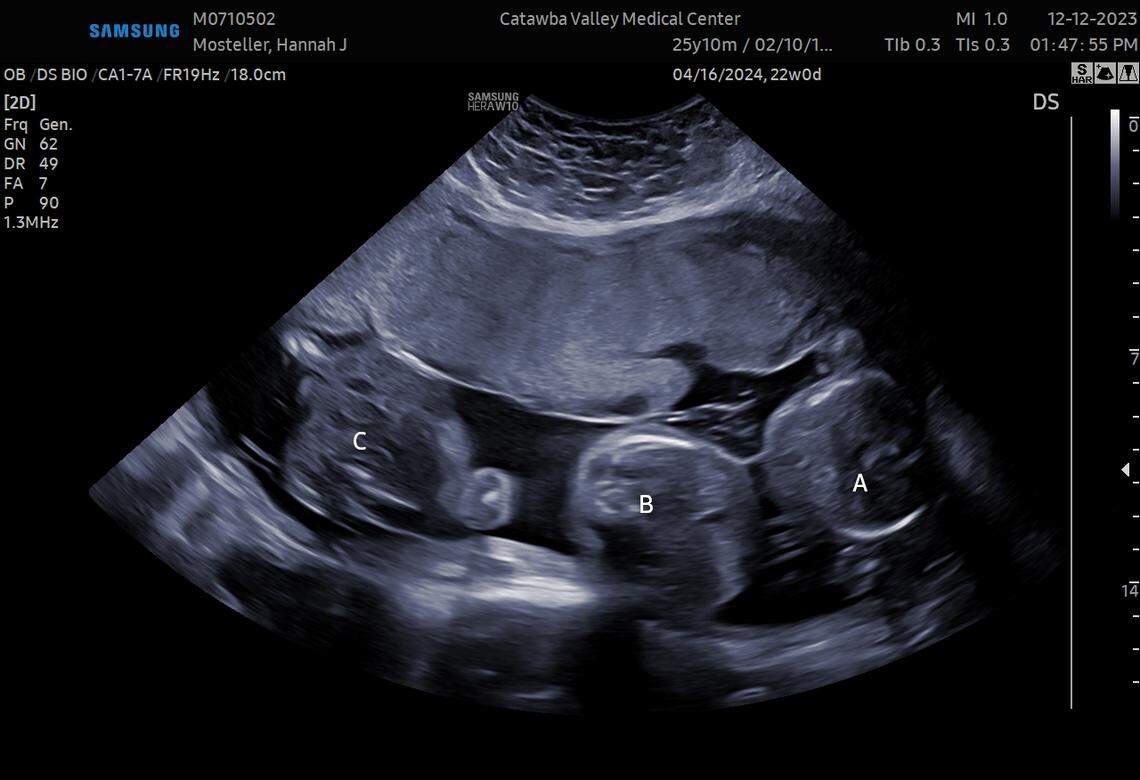

The first ultrasound, showing the Mosteller triplets.

The first ultrasound, showing the Mosteller triplets. Courtesy of Hannah Mosteller

Stacy knew her niece had gone to Heartbeats, and when her daughter Jasmine called to say Hannah was done with her appointment and wanted to talk to them at the same time, Stacy braced herself for bad news. Oh gosh, this is not good, she thought. Hannah must have had a miscarriage. “But we got on Facetime, and they showed the ultrasound picture. ... Then I saw the labels — ‘A,’ ‘B,’ ‘C’ ... and at first I thought they were just labeling, like, the arms, legs, head. ... Then it hit me. I was like, ‘THREE BABIES??’”